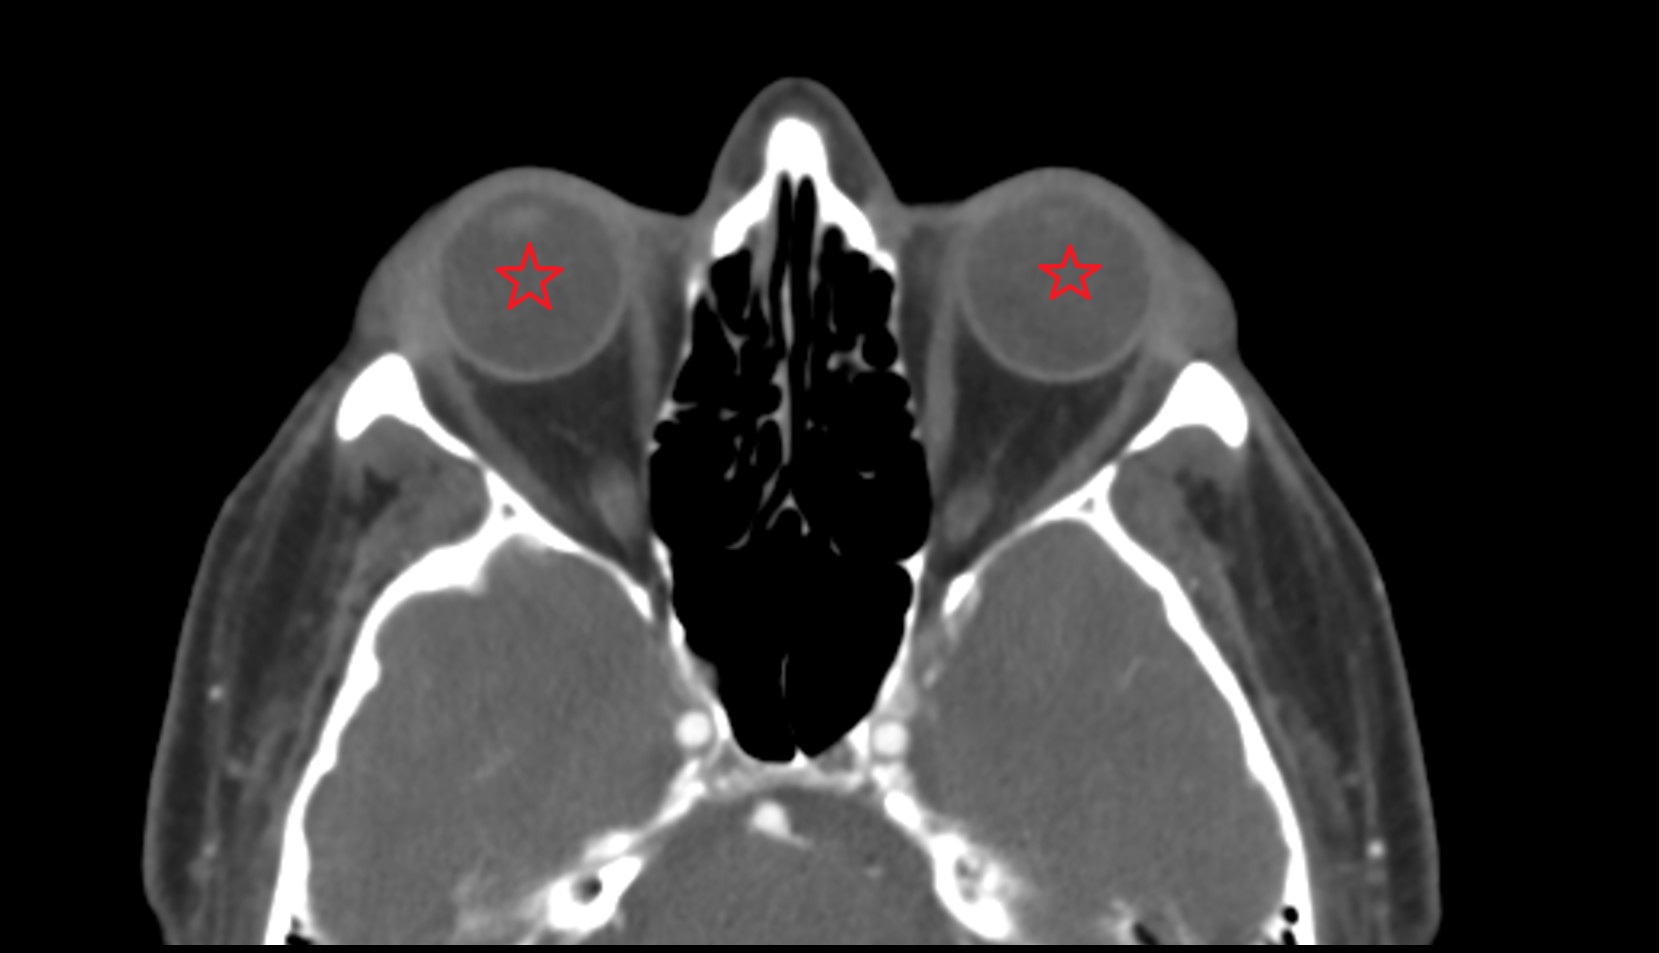

- lens of the eye

- Cornea

- Iris

- Pupil

- Anterior chamber of eyeball

- Posterior chamber of eyeball

- Vitreous chamber of eyeball

- Sclera

- Choroid

- Retina